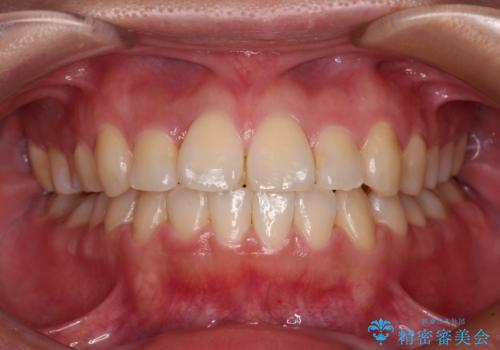

反対咬合とクロスバイトを改善して噛みやすい咬合に

- 前歯のデコボコとクロスバイトを気にして来院された患者様です。

骨格的に下顎が前方位の受け口傾向であり、それが原因でクロスバイトとなっていました。